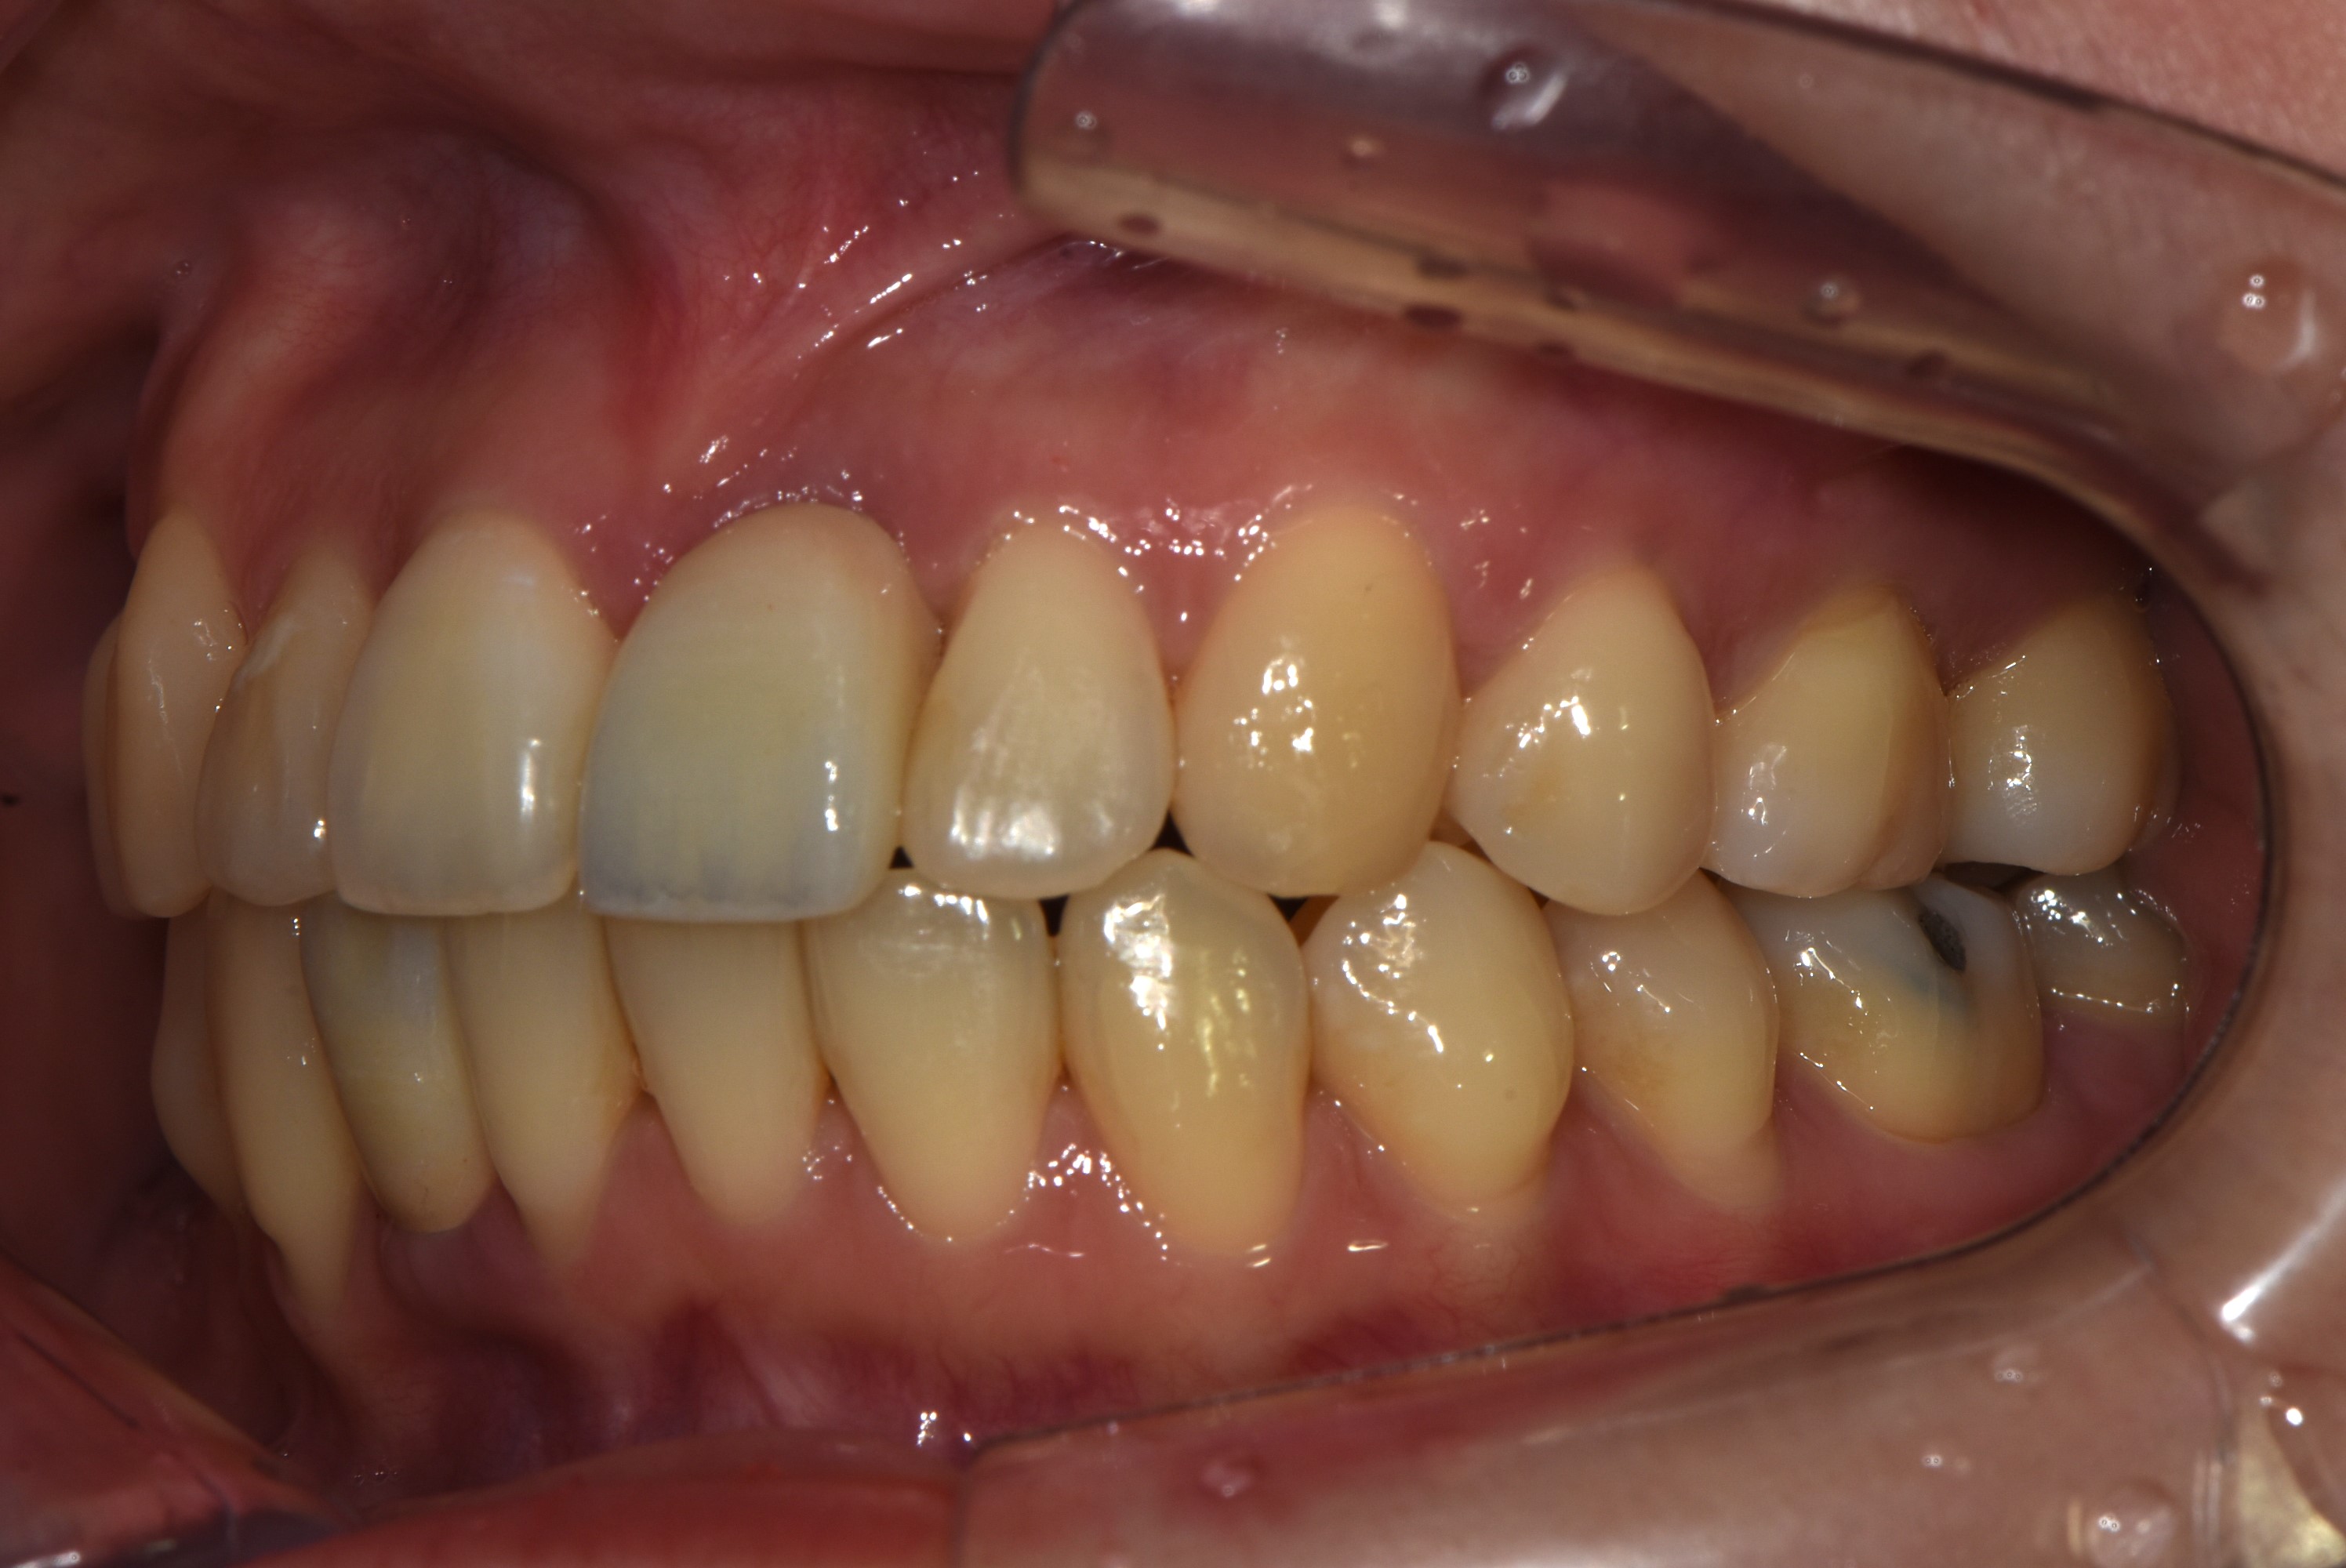

치료 전 사진입니다.